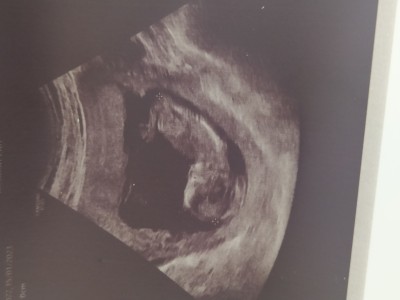

imageKızlar doktor birşey söylemedi kendi doktorum yoktu bu da doğru düzgün ilgilenmedi bile soramadm

Kaç haftalık ben erkeğe benzettim

(38 puan) tarafından

Hayırlısı sağlıklı olsun da ilk bebeğimi kaybedince yeterki sağ salim kucağıma alabileyim

Tahmininiz doğru çıktı oğluşum geliyor Allah'ım nasip ederse